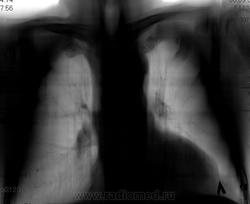

Не ясный...  В клинике превалирует одышка...

Отмечает внезапно возникшую одышку? ЭХО-КГ было? Мне чудится симптом Вестермарка в верхней доле справа и нежная интерстициальная инфильтрация в S6 справа. Хвост правого корня не красивый, может он "обрублен"? Ну и признаки ХОБЛ есть.

Тень сердца объясняет причину одышки.

Коллеги, а как Вы объясните эту тень? Что-то я на ней зависла. Не ателектаз, не междолевой плеврит. Абдоминомедиастинальная липома?

Тень это жир, по прямому тоже хорошо видно что сердце жирновато

Попробую объяснить. Стрелок на картинках не нарисую, по причине что я сейчас однорукая (отдыхаю на больничном со сломаной правой). Я не настаиваю на своем мнении, мне только "почудилось". Если сравнивать лег рисунок верхних долей, то справа он мне кажется обедненным. Для такого-то сердца и сосудов по лег полям должно быть поболее. А интерстиц инфильтрация, потому что нет "пятен" и "хлопьев" сливающейся альвелярной (простите КТ-шный термин), а есть нежное сетчатое затемнение, на фоне которого прослеж сосуды. Вот дисковидных коллапсов я не нашла, покажете?

Как-то сомневаюсь я в абдоминомедиастинальной липоме. Огроменные размеры, фестончатый контур. Подумала ещё о парастернальной диафрагмальной грыже. Валентин Львович, а в архиве что?